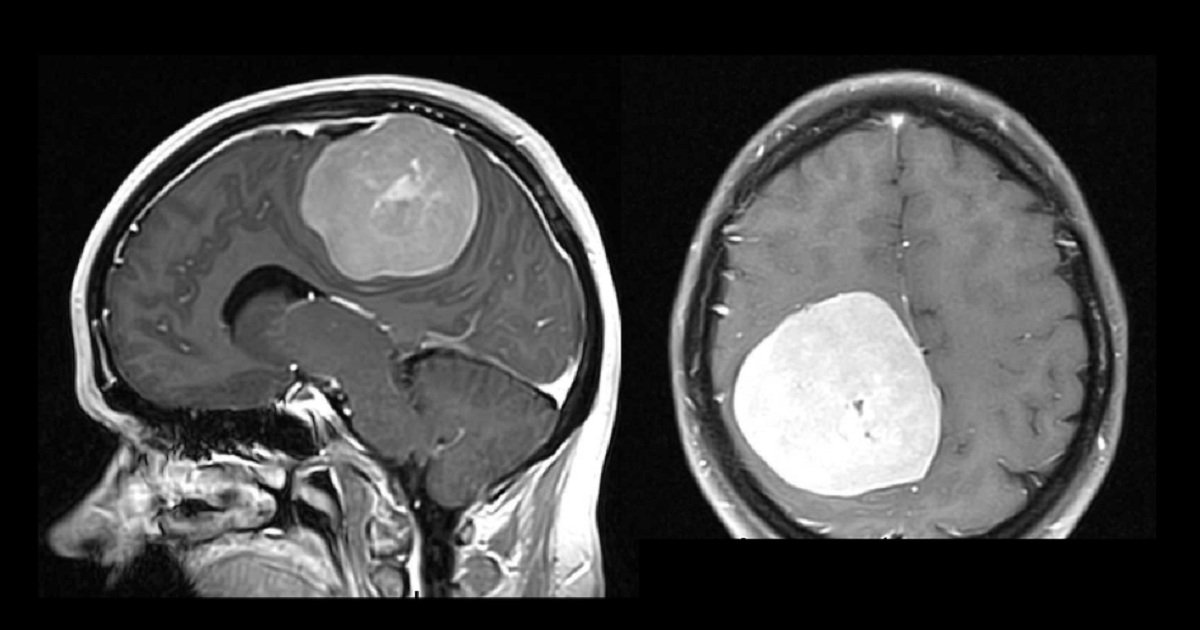

tumor otak sendiri adalah pertumbuhan sel-sel otak yang luar biasa dan tidak terkawal. Dalam otak, tumor boleh membangunkan dari sel-sel yang membentuk tisu otak, saraf yang keluar-masuk ke dalam otak, dan membran yang meliputi otak dan saraf tunjang (meninges). Pada asalnya, tumor otak dibahagikan kepada dua, iaitu primer dan sekunder. Tumor otak primer adalah tumor yang timbul dalam otak, manakala tumor otak sekunder adalah ketumbuhan yang berasal dari bahagian-bahagian badan yang lain tetapi merebak ke otak.

Kebanyakan kes kanser otak adalah sejenis kanser otak sekunder, di mana kanser yang berasal daripada organ lain dan kemudian merebak ke otak. Apabila dilihat dari tahap pembangunan dan mempercepatkan pertumbuhan dan penyebaran, ketumbuhan malignan tumor otak dibahagikan kepada empat peringkat, iaitu: